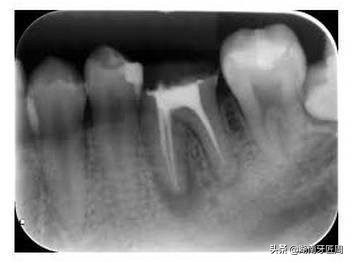

牙齿在牙片上显示出白色阻射影像,牙釉质阻射最强,牙本质和牙骨质阻射低于牙釉质,牙髓腔呈黑色透明影像,根管口至根尖孔呈逐渐变细的影像。